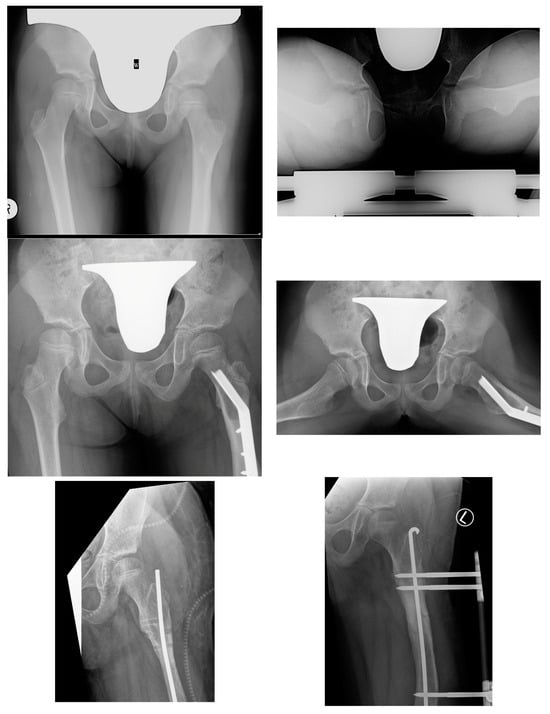

The key clinical information about hip instability cases is summarized in Table 9. Figure 4 shows radiograms and CT scans of the case of hip joint instability after femoral lengthening (Case 2).

Figure 4.

Patient with hip joint instability after femoral lengthening. The first row shows radiograms at initial evaluation with diminished antetorsion on the right radiogram. The second row shows radiograms after hip preparatory surgery. The third row shows radiograms after removal of the external fixator (left side) and after treatment of the femoral fracture—Rush rod with external fixator (right side). The fourth row shows radiograms the first post-op day after removal of the Rush rod, with visible left hip joint dislocation. The final and fifth row shows radiograms 1 year after surgical treatment—the left hip joint remained stable (last follow-up—over 4 years post-surgical treatment of dislocation).